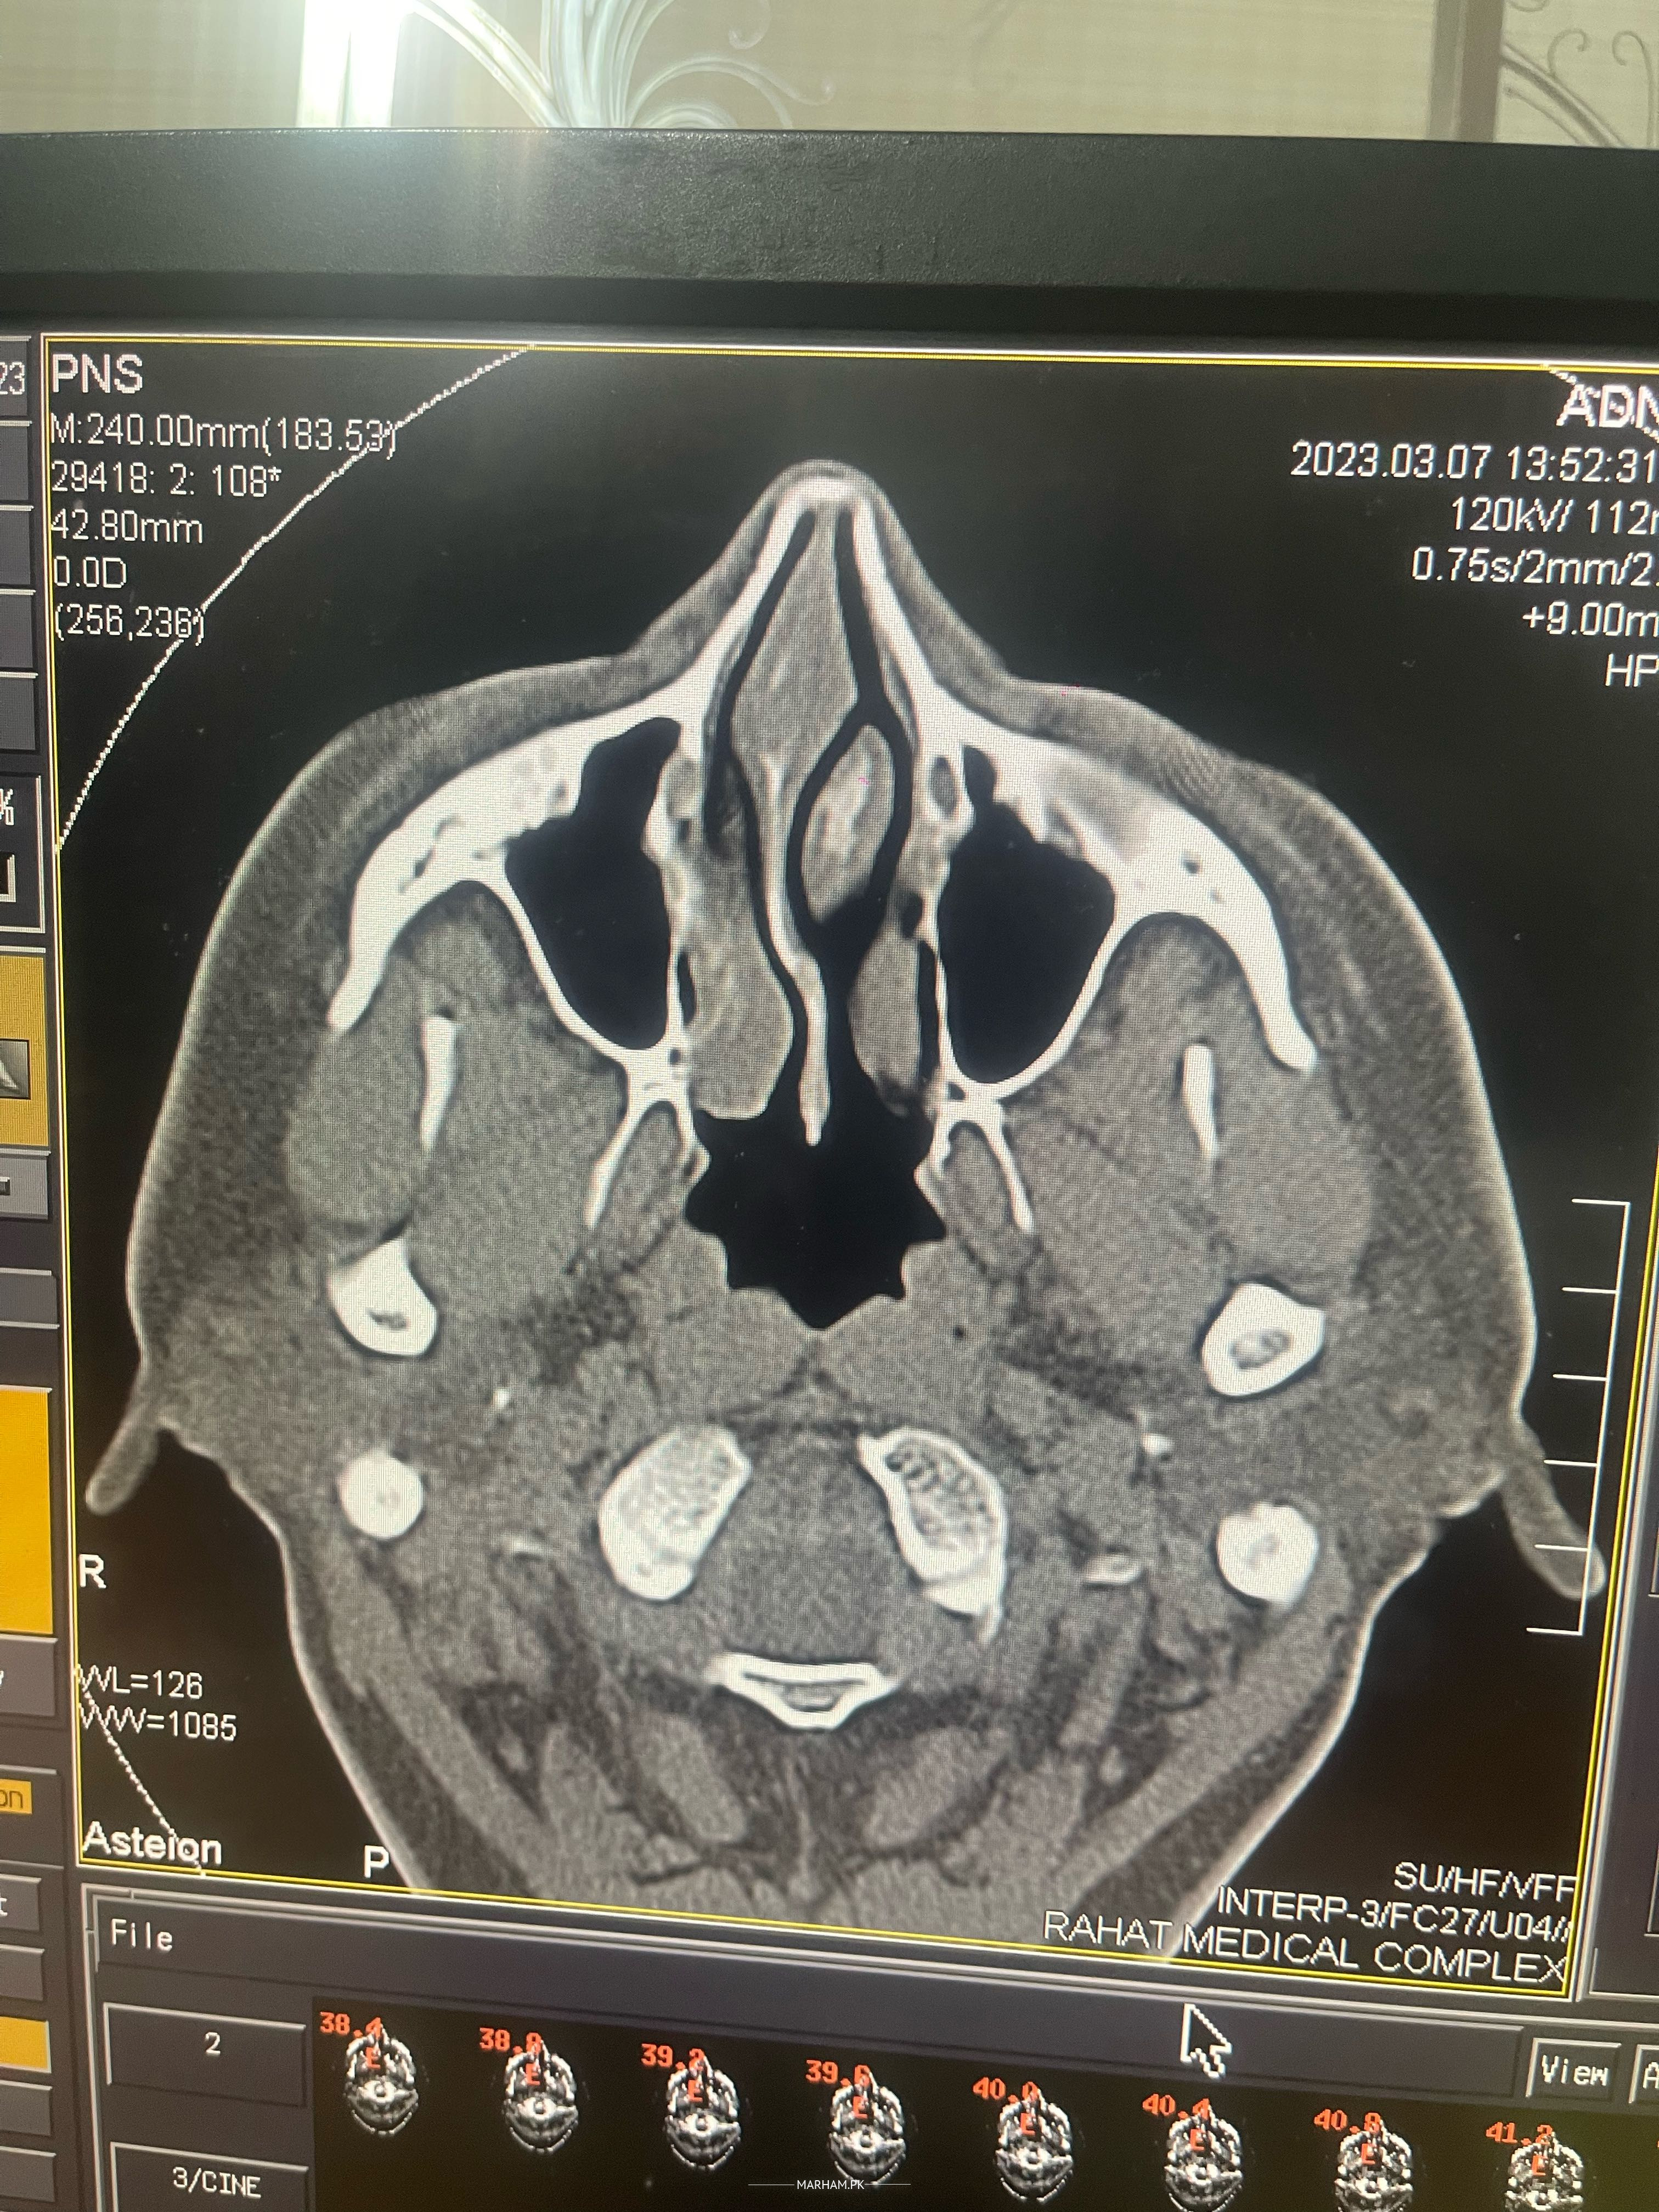

Talk to Ent Specialist on Nose Blockage With Tinatus

Asking For Self, Male, 30 Years old, peshawar

Nose may kharish hota hai ankho say pani ata hai sard dard hota rehta hai Marham say dr ka video consaltant leya ta dr. K sath share b kia lekn 24 tak koi reply ni aya